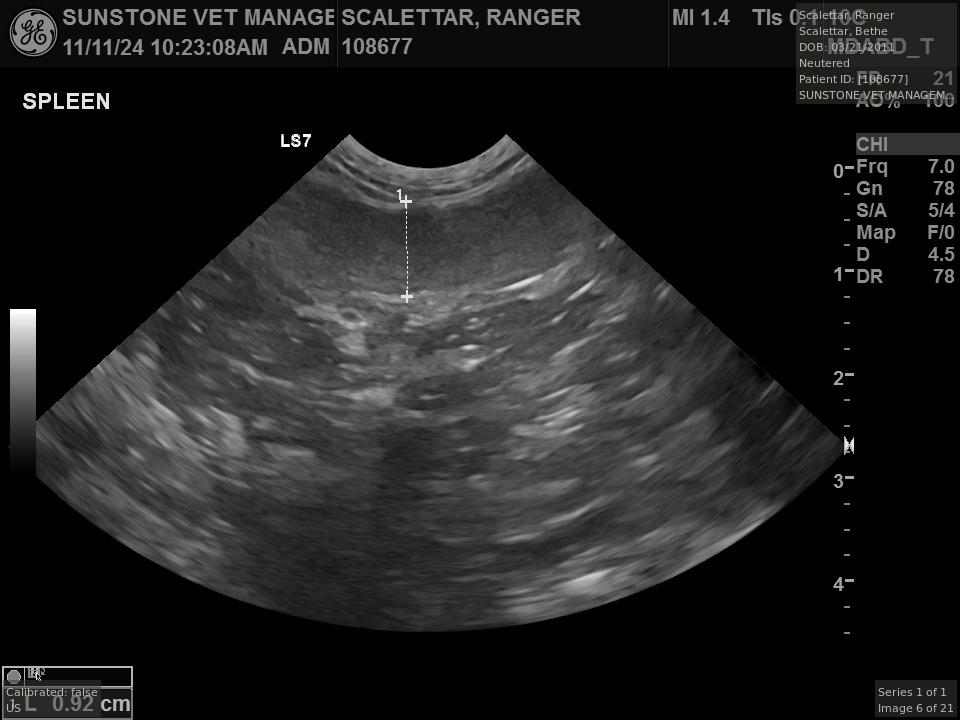

Veterinary ultrasound examinations of the thorax and/or abdomen typically include a number

of views selected to assess the health and function of internal organs. Unlike with radiography,

the images do not include the lungs because ultrasound reflects off the outer boundaries of the

lungs, making it difficult to see inner structures.

The veterinarian generated a series of images showing different organs and substructures by

changing the position and orientation of the ultrasound transducer. The images were collected

in a defined order, which is repeated from patient to patient, ensuring that nothing is missed. In

Ranger's case, the sonographer collected about twenty images during an examination that

lasted about fifteen minutes.

The sonographer stated that Ranger's ultrasound images were largely normal for an older cat. In particular, they show changes in the kidneys that are commonly noted in geriatric cats and that reflect a risk for the development of chronic kidney disease. However, the images did not show any significant abnormalities in Ranger's stomach, intestines, and associated lymph nodes. Nonetheless, the results did not rule out recurrence of Ranger's small cell lymphoma.